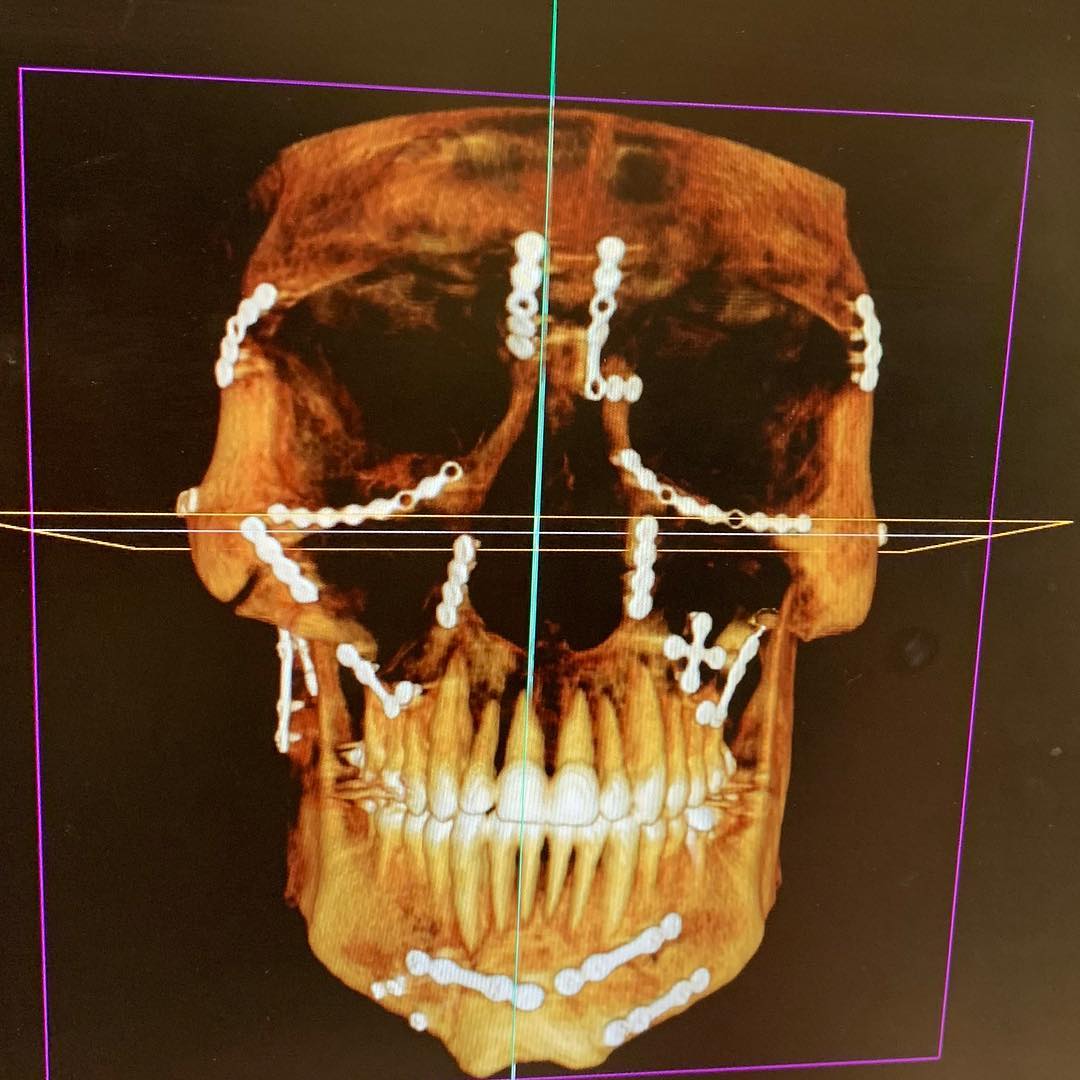

Weston Peick mostra a reconstrução do seu rosto

Weston Peick mostrou o quanto de trabalho foi necessário para reconstruir seu rosto após o acidente no Supercross de Paris, em novembro.

“21 placas quatro parafusos e um enxerto ósseo”, disse Peick sobre a cirurgia que ele teve que suportar após ser atropelado no primeiro main event da noite. Peick se recuperou bem, mas não foi divulgado se ele poderá voltar a competir.